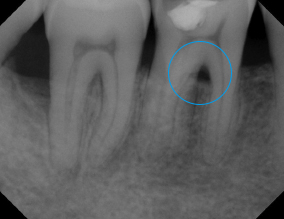

Ozone Treatment :

Bone healing with ozone treatment and SRP

Reverse Gum Disease: Bone Healing